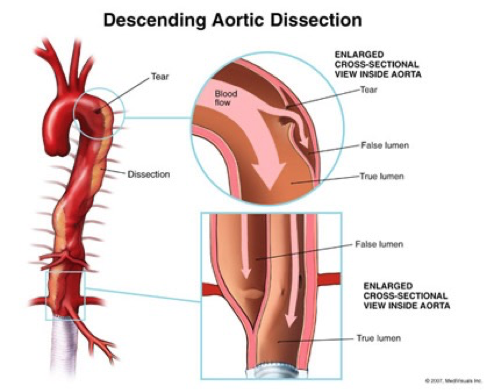

Aortic dissection

Tear in the inner wall of the aorta (intima) causes blood to flow into the middle layer (media) and force the layers apart

What does this refer to (in terms of aortic dissection)

Most simplified classification system EVER!

Stanford system divided into:

Stanford Type A (proximal)

_______________

Involves the Ascending aorta

What does this refer to (in terms of aortic dissection)

Most simplified classification system EVER!

Stanford system divided into:

Stanford Type B (distal)

__________

Does NOT involve the ascending aorta

What does this refer to

Stanford Typing System Aortic Dissection

Most commonly in the aortic arch or L subclavian

Always include in differential of chest pain

Typically c/o severe sharp, “tearing” (ripping) sensation in the chest or back

Be suspicious of dissection in high risk patients c/o pain radiating to the back

Pain may migrate as the dissection extends

Stanford Type A-chest pain anteriorly—may hear new murmur in aortic area

Stanford Type B-may see pain between scapular areas/back pain.

Neck or jaw pain may occur with involvement of aortic arch